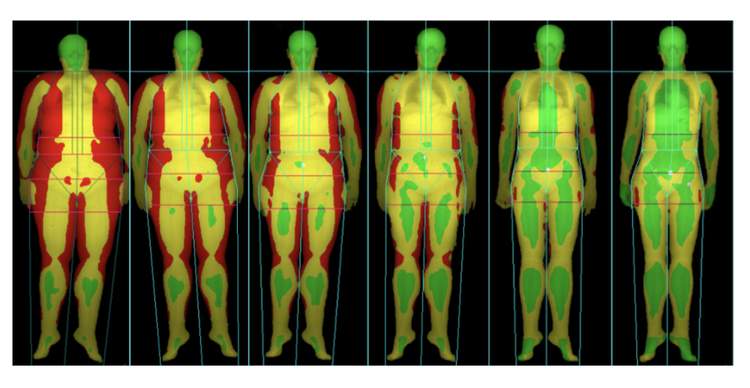

L’analyse de la Masse grasse et des graisses viscérales en bio-impédancemétrie